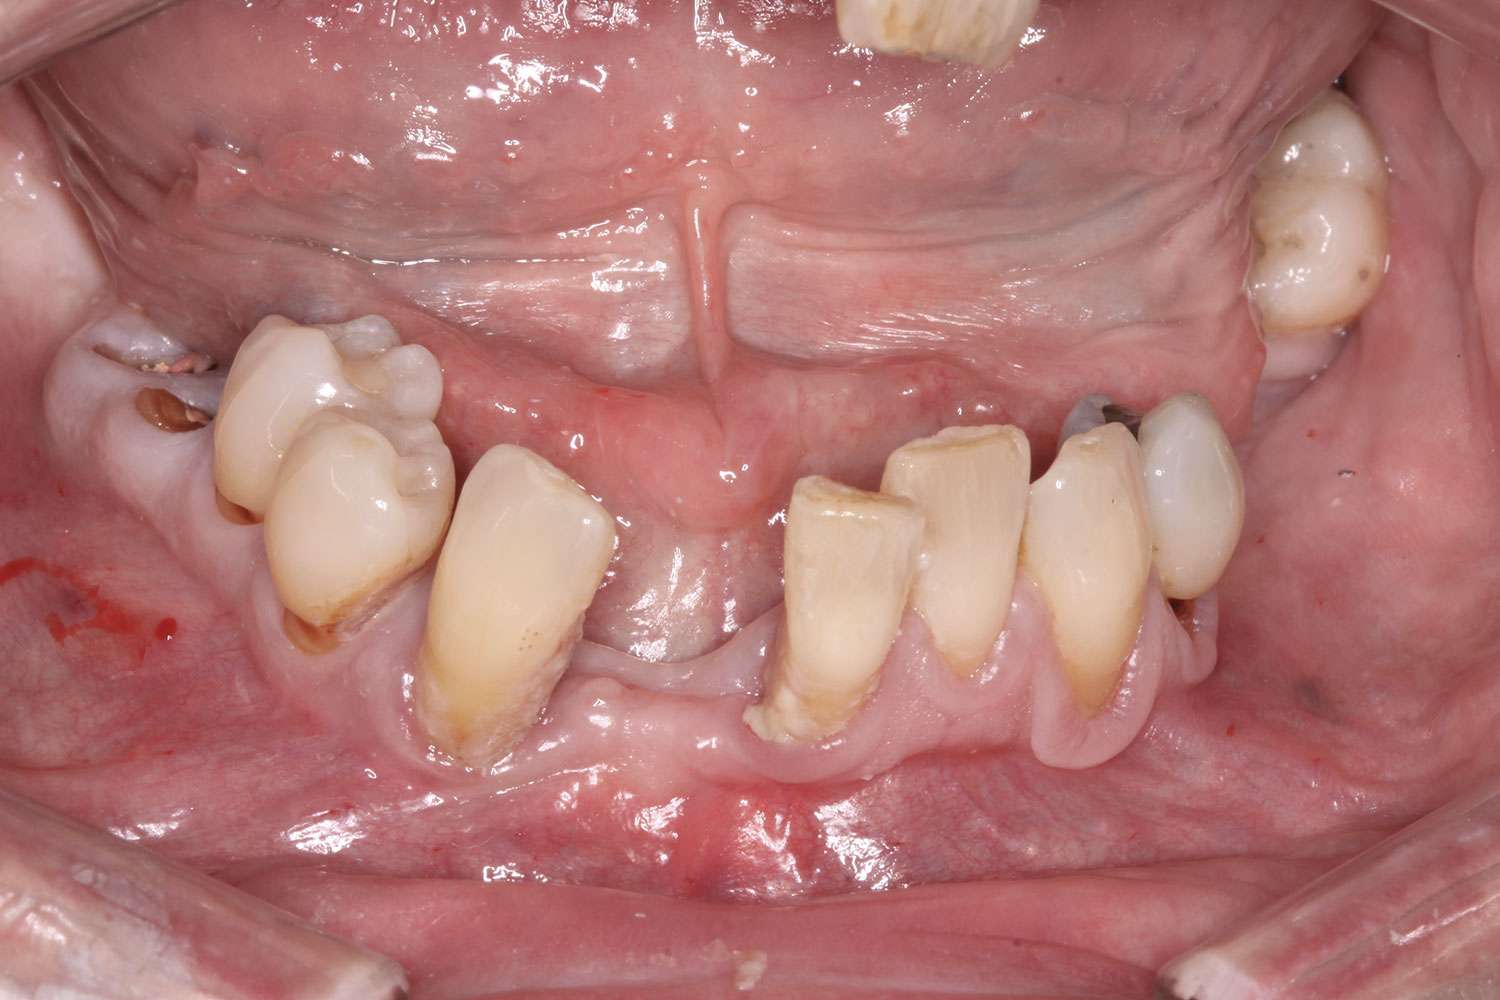

A 60-year-old female patient presented with many periodontally and restoratively hopeless teeth that severely compromised esthetics and function and were inadequate to retain a maxillary restoration. She declined to advance into a full maxillary denture or partial denture. Existing maxillary teeth included Nos. 2 and 4 through 14 (Figure 9 and Figure 10). The opposing dentition was stable. The patient was in good health with no allergies to medication.

Fig 9. Case 2: Initial presentation for maxillary immediate implant, immediate load provisional restoration. Full-face photograph.

Figure 9

Fig 10. Initial clinical situation, intraoral view.

Figure 10